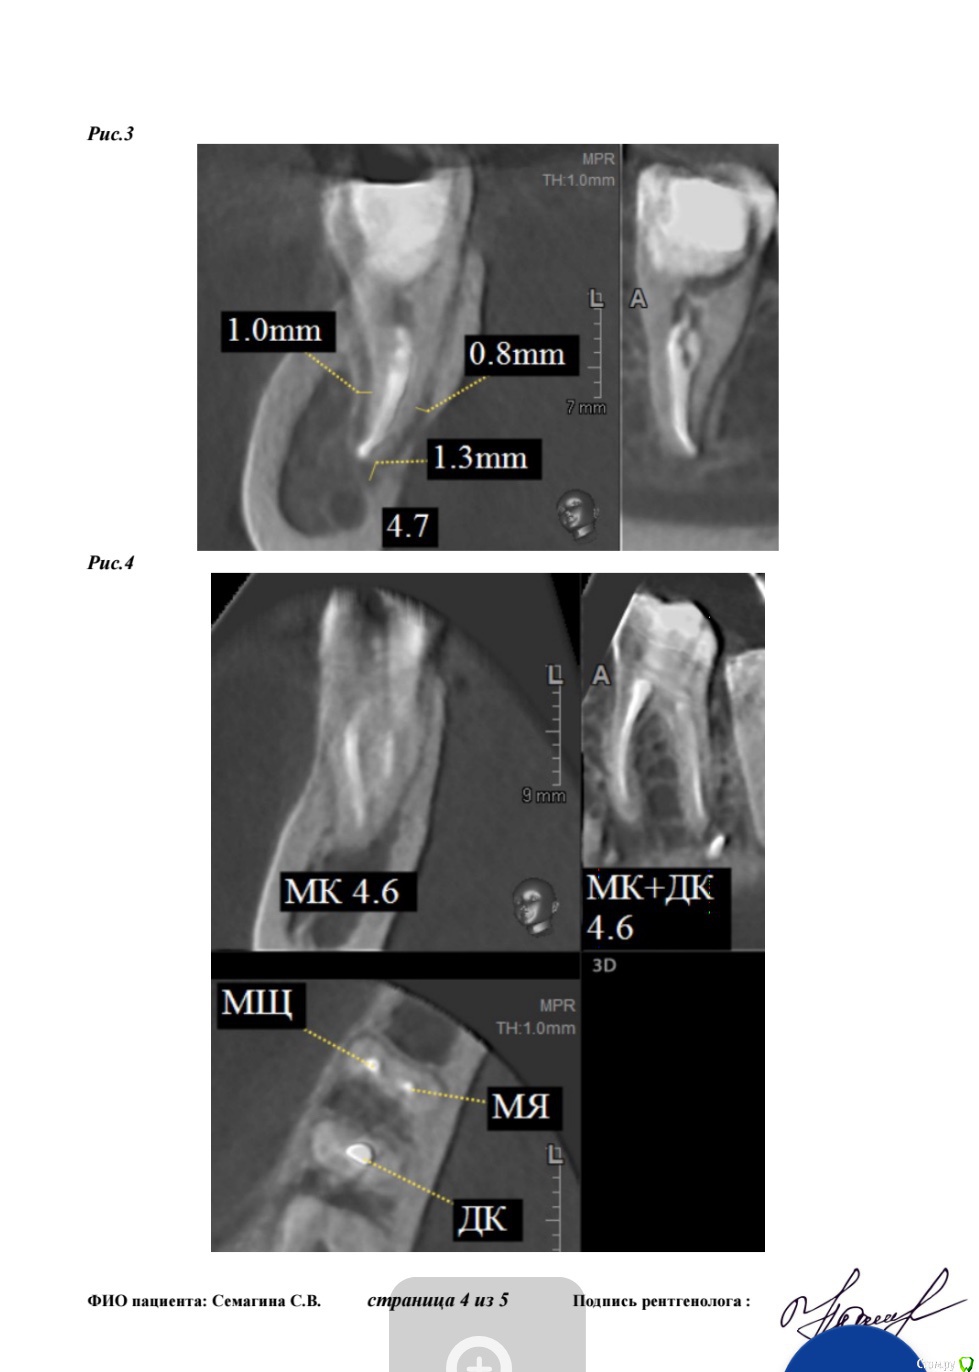

Лана-Лана Опубликовано 14 февраля, 2018 Поделиться Опубликовано 14 февраля, 2018 (изменено) Зуб семерка справа нижний, перелечивался после перидонтита... состояние такое как на кт, сам не болит но жевать невозможно, есть ли смысл перелечивать ? Очень хочу зуб сохранить... запломбированн на одну треть .. место под вкладку . На данный момент все таки раскрыли поставили метопасту. Изменено 14 февраля, 2018 пользователем Лана-Лана Ссылка на комментарий

Лана-Лана Опубликовано 15 февраля, 2018 Автор Поделиться Опубликовано 15 февраля, 2018 (изменено) Сейчас зуб в таком состоянии с метапиксом( перепутала изначально сказала метопаста), вижу темное пятно слева от зуба это что воспаление? И так же вижу слева как второй корень именно корень а не канал... он как бы чуть чуть выглядывает из за первого корня , или это наслоение какое то?. в первом корне 2 канала а может быть в другом корне тоже какой то патайной канал которого воачи не видят ? Изменено 15 февраля, 2018 пользователем Лана-Лана Ссылка на комментарий

Лана-Лана Опубликовано 17 февраля, 2018 Автор Поделиться Опубликовано 17 февраля, 2018 Зуб стал болеть с метапиксом такая давящая ноющая, припухлость не уходит! Что делать дальше? Ждать ? Сказали ходить три недели! Или пойти поменять лекарство? Уважаемые доктора посмотрите последний снимок почему лекарство не до апекса? Оно вообще как то подействует на воспаление в кости в десне? Может ли быть в таком зубе третий канал скрытый? Может какой то внутри разделяется на два? По кт может что то видно? Ссылка на комментарий

Лана-Лана Опубликовано 21 февраля, 2018 Автор Поделиться Опубликовано 21 февраля, 2018 Ну почему ни кто не отвечает((( вчера достали метопасту так как зуб болел ... промыли и поставили крезофен сказали посмотрим на герметичность ... что если герметичности нет то и с крезофеном будет болеть... не знаю правильно ли я это все поняла и сформулировала... но как то так... зуб стал лучше , конечно не в идеале но лучше??? В чем секрет крезофена? На кальции так зуб не проходил... может у меня там дополнительные каналы внутри отростки от основных... вообще не понимаю что с зубом происходит((( Ссылка на комментарий